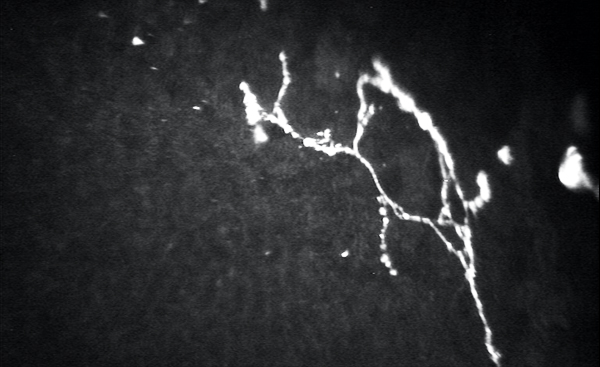

Confocal microscopy has great potential to help document the source of peripheral neuropathic pain (Figure). The ability to obtain details regarding nerve density, tortuosity, neuromas, and beading can help researchers, physicians, and patients work together to improve and heal these delicate neurons.9-12,15 Hopefully, just as other imaging technologies have improved exponentially in the last decade, so will our ability to document and monitor these neurologic pathologies.

Figure. Confocal microscopy of the basal nerve plexus demonstrating corneal beading, branching, and neuromas in a patient with neuropathic corneal pain.